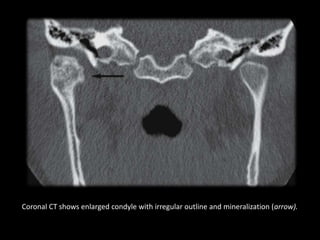

Coronal CT shows enlarged condyle with irregular outline and mineralization (arrow).

Coronal CT showsenlarged condyle with irregular outline and mineralization (arrow).